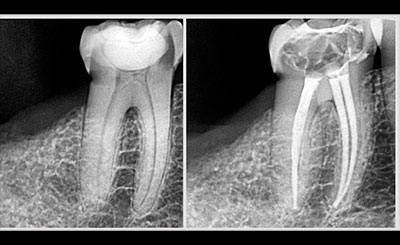

Root canal treatments

Root canal treatment is an often straightforward procedure to relieve dental pain and save your teeth. Patients typically need a root canal when there is inflammation or infection in the roots of a tooth.